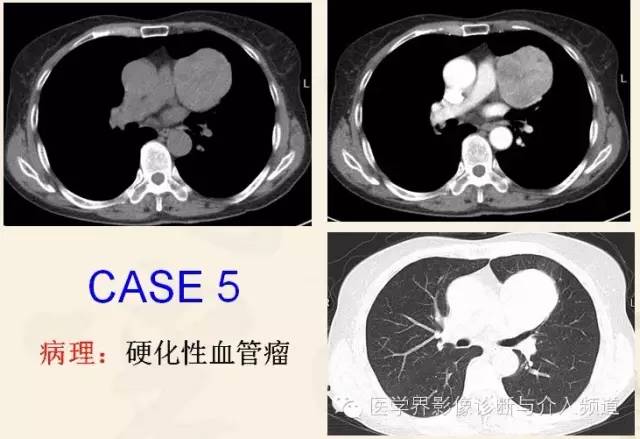

硬化性血管瘤(PSH)

肺部少见的良性肿瘤,在所有肺肿瘤中占的比例为1%。关于肿瘤的起源过去有不同的假说,最近超微结构及免疫组化认为该病起源于肺泡上皮增生,特别是II型肺泡细胞。多发生于中青年女性患者(30~50岁)。

目前虽多数学者认为其属于良性肿瘤,但亦有其向周围间质或支气管浸润、立方细胞表达癌胚抗原(CEA)和淋巴结转移的报道。

CT表现

平扫:具有一般良性肿瘤的特点,表现为边界清晰,光滑锐利,圆形或类圆形结节或肿块。少数可有轻分叶,无毛刺征象。

肿瘤内不同组织成分决定了其CT密度差异,高密度区为瘤体内血凝块充填的海绵状血管瘤区;等密度为瘤体内的实体部分;低密度区为瘤体内充满黄色液体的囊性区。

内部可见散在钙化点,部分病灶内可有大片不规则的钙化,但其内部无脂肪成分。

强化:小病灶以血管瘤型和乳头型为主,血管密度高,所以强化显著。而随着病灶增大,以实性区为主的肿瘤具有持续且延迟强化特点。随着病程进一步延长,以出血型为主的肿瘤内的实体型和硬化型结构逐渐增多且分布不均,该区域内血管数目相对减少,从而表现为不均匀性强化。